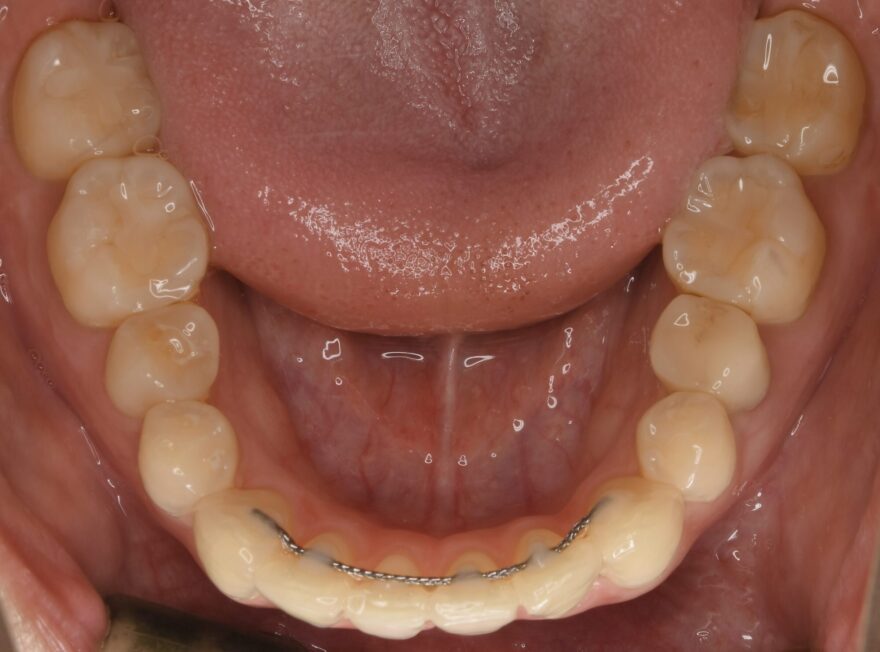

治療後の口腔内写真

約2年半の動的期間(歯を動かす時期)で、ここまで美しい歯並びになりました。

歯科矯正用アンカースクリュー無しだと、治療期間は更に1年長くなってしまったと思います。

前歯の捩れも無くなりました。

上顎の前歯にはワイヤーによる保定装置を装着しました。

こちらもの前歯にはワイヤーによる保定装置を装着しました。